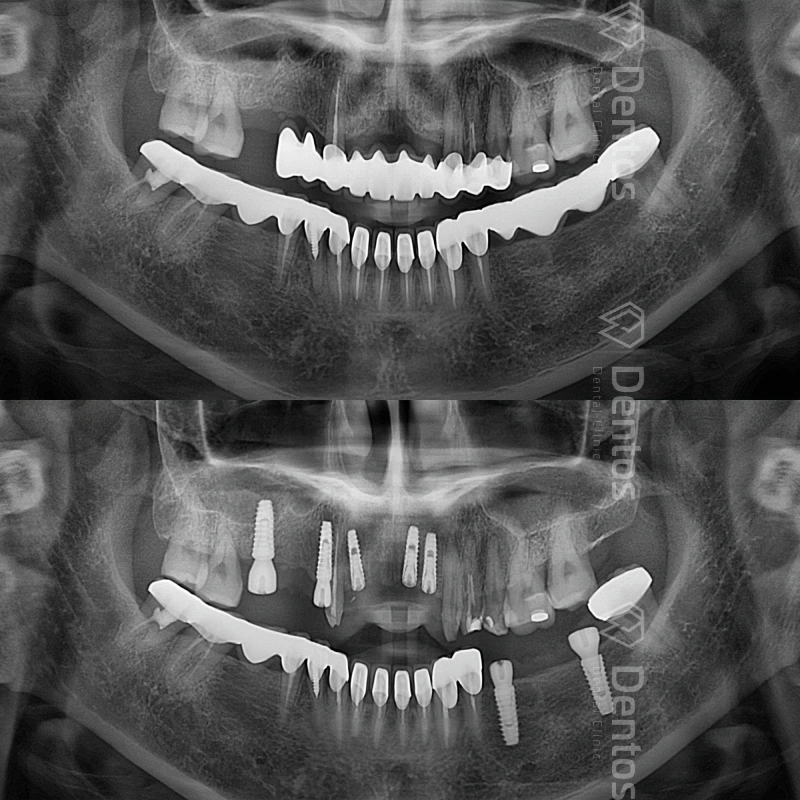

Dentos thực hiện thành công hàng ngàn ca răng toàn hàm và đơn lẻ.

Chụp phim CT Conebeam 3D - Kỹ thuật xuất phim 3 chiều của mô răng, mô mềm, xương hàm và ống thần kinh để đưa ra kế hoạch điều trị.